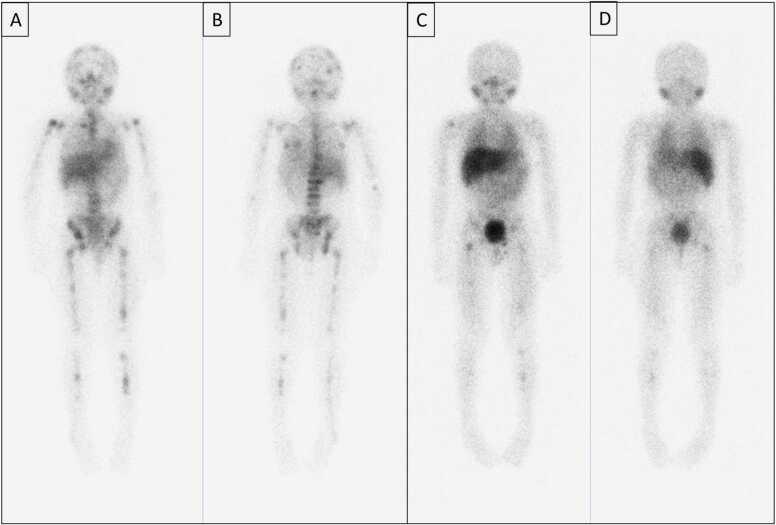

As new molecular tracers are identified to target specific receptors, tissue, and tumor types, opportunities arise for the development of both diagnostic tracers and their therapeutic counterparts, termed "theranostics." While diagnostic tracers utilize positron emitters or gamma-emitting radionuclides, their theranostic counterparts are typically bound to beta and alpha emitters, which can deliver specific and localized radiation to targets with minimal collateral damage to uninvolved surrounding structures. This is an exciting time in molecular imaging and therapy and a step towards personalized and precise medicine in which patients who were either without treatment options or not candidates for other therapies now have expanded options, with tangible data showing improved outcomes. This manuscript explores the current state of theranostics, providing background, treatment specifics, and toxicities, and discusses future potential trends.

随着新的分子示踪剂被确定用于靶向特定受体、组织和肿瘤类型,开发诊断示踪剂及其治疗对应物(即“治疗诊断剂”)的机会应运而生。诊断示踪剂利用正电子发射体或γ发射放射性核素,而它们的治疗诊断对应物通常与β和α发射体结合,这可以将特定的局部辐射传递到靶点,同时对未受影响的周围结构造成最小的附带损伤。这是分子成像和治疗领域令人兴奋的时期,也是迈向个性化精准医学的一步,在这种医学模式下,那些原本没有治疗选择或不适合其他疗法的患者现在有了更多选择,切实的数据表明治疗效果有所改善。本文探讨了治疗诊断学的现状,提供了背景、治疗细节和毒性,并讨论了未来的潜在趋势。